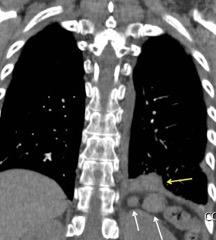

25. DERRAME PLEURAL. TRAUMA

26. DERRAME PLEURAL UNILATERAL. ENF. SUBDIAFRAGMÁTICA

Hemorrágica………….30-70 UH

Extravasación iv. con sangrado activo……….>90 UH

“Simpático”………….,,,,<15 UH

Durso AM et al. Penetrating Thoracic Injury. Radiol Clin N Am 2015.

En el hemotórax, los elementos formes de la sangre tienden a depositarse en la parte más declive

Polireddy K et al. Blunt thoracic trauma: role of chest radiography and comparison with CT findings and literature review . Emerg Radiol 2022.